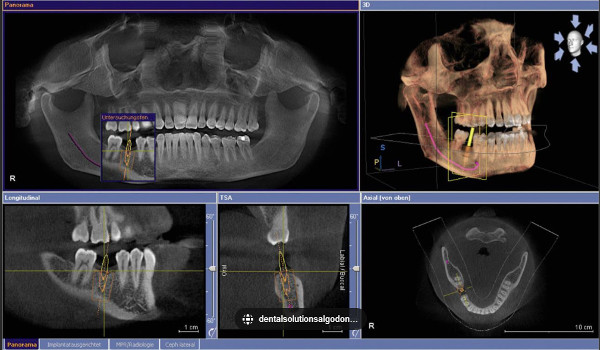

Our practice utilizes state-of-the-art, full cranial cone-beam CT (computed tomography) technology that provides highly accurate 3-D radiographic images for the diagnosis, planning, and treatment orthodontics, implantology, TMJ analysis, oral and orthognathic surgery and other dental procedures. Undistorted, anatomically correct view of the jaws, teeth, and facial bones along with corss-sectional (bucco-lingual), axial, cororsagittal, cephalometic and panaoramic views are easily generated. Three-dimensional images enable a level of anatomical acuracy and patient care not possible with 2-D technologies.